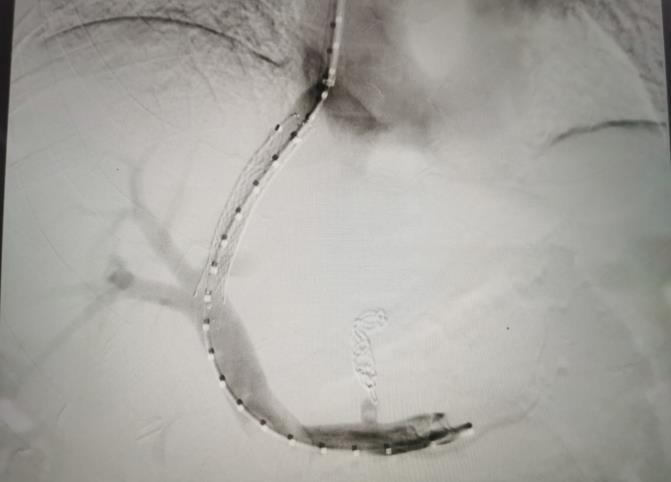

經(jīng)過(guò)我院血管介入科醫(yī)療團(tuán)隊(duì)的精心準(zhǔn)備,患者在數(shù)字減影血管造影機(jī)(DSA)導(dǎo)引下,順利經(jīng)頸靜脈入路進(jìn)入下腔靜脈并成功穿刺了門(mén)靜脈右支主干,術(shù)中栓塞了曲張的胃冠狀靜脈-食管靜脈叢將支架植入肝實(shí)質(zhì)內(nèi),支架兩端分別置于門(mén)靜脈和肝靜脈內(nèi),術(shù)程歷時(shí)2小時(shí),術(shù)中患者時(shí)刻保持清醒,手術(shù)切口僅5毫米,術(shù)后第2天恢復(fù)飲食,腹脹、腹水癥狀明顯好轉(zhuǎn),未出現(xiàn)嘔血、黑便及肝性腦病等并發(fā)癥,術(shù)后第3天康復(fù)出院。